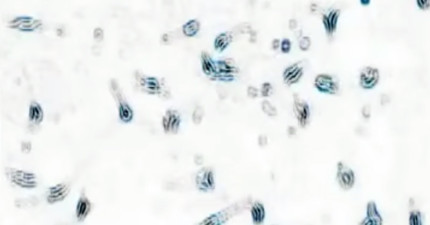

這就是將大麻注入癌細胞後會發生的醫學奇蹟!